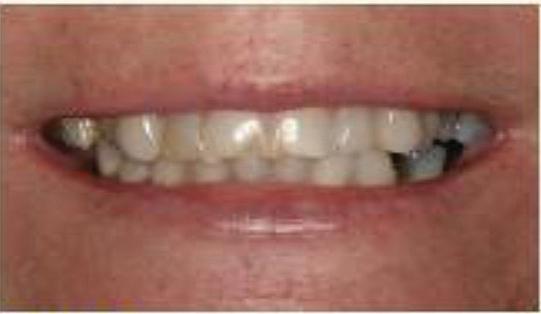

Can just four implants replace all of the teeth on the top or the bottom of your mouth? Thanks to advances in dental implant technology, that answer is a resounding yes.

Tooth loss is extremely common among adults, especially as we age. Rather than living with the discomfort and hassles of dentures, many people are opting for what is called “all-onfour” dental implant restoration.

An implant is a small titanium screw

that fits inside your jawbone and replaces the root-part of a missing tooth. Minor surgery is required to insert the implants. Once the implant is in place, a crown is attached to give you a highly realisticlooking and functional prosthetic tooth.

You do not need a dental implant for each and every one of your missing teeth. All you need is four precisely placed implants on the top of your mouth, and four on the bottom, to restore your full smile. That’s the beauty of the all-on-four. And because the implant is made of titanium, it has the unique ability to fuse to living bone and function as part of it. So eventually, the dental implant becomes part of the jawbone and serves as a strong, longlasting foundation for your new teeth.

Besides ensuring that your implants are permanently fixed in place, this bone fusion has another important benefit: it prevents future bone loss in the jaw. This helps to maintain a more youthful facial structure – and better oral health. But perhaps the biggest

Please see “All-On-Four,” page 61